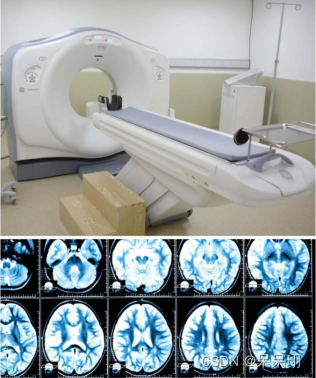

3. CT(计算机断层扫描)

1. 概念:CT利用X射线和计算机技术来创建身体的详细横截面图像。它通过多个角度的连续扫描,产生多个切片图像,可以提供更详细的结构信息。

2. 优点:

- 高分辨率:CT可以提供高分辨率的图像,显示细小结构和病变。

- 快速扫描:CT扫描速度较快,适用于紧急情况下的快速诊断。

- 多平面重建:CT图像可以进行多平面重建,提供更全面的解剖信息。

3. 缺点:

- 辐射暴露:CT需要使用较高剂量的X射线,辐射剂量相对较高,需要慎重考虑。

- 对部分人群有限制:CT对于孕妇和儿童等敏感人群的使用有限制。

- 对金属伪影敏感:CT对金属假体或金属物体的存在敏感,可能产生伪影。

4. 应用:CT常用于疑似肿瘤、颅脑损伤、胸部疾病、腹部疾病等的诊断。